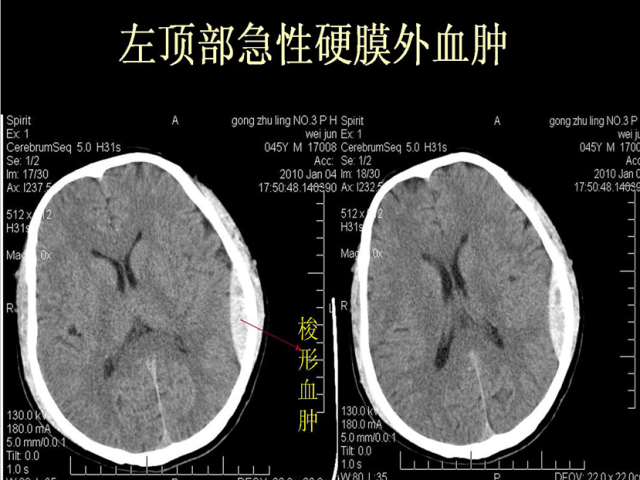

急性颅脑损伤篇

03